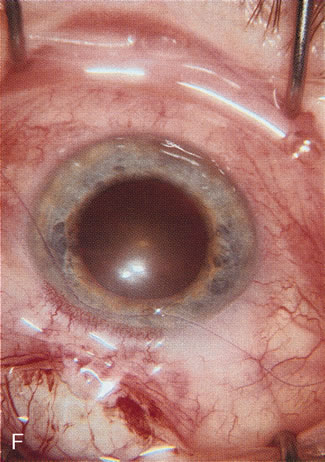

A patient with long-standing primary open-angle glaucoma with a successful glaucoma filtration procedure and IOP of 10 mm Hg on no antiglaucoma medications develops a significant, moderately dense nuclear sclerotic cataract. This patient is best served by small incision cataract extraction with foldable IOL implantation. Less desirable options include ECCE with IOL implant via clear cornea, temporal limbus, or inferior approach. Astigmatism, wound instability, prolonged visual recovery, visual fluctuation, exposed sutures, and bleb failure are the major drawbacks to large-incision lens extraction. Even after the surgeon has mastered large-incision clear corneal cataract extraction, long-term wound shift and astigmatism are a chronic problem (Fig. 6). Inferior cataract extraction is difficult for those not experienced with it. With the advent of small-incision phacoemulsification surgery, the surgeon is now able to use a limbus approach adjacent to the bleb or a clear corneal temporal approach. Postoperative inflammation is less with the smaller incision, and filtering blebs are more likely to survive. Patients with IOP greater than 10 mm Hg after a filtering procedure are more likely to experience permanent IOP elevation after phacoemulsification. Patients should understand that IOP elevation post cataract extraction is always an issue, even with a functioning filter.

Fig. 6. ECCE following trabeculectomy. The larger corneal incision associated with ECCE leads to a host of problems that are typically less severe with small incision cataract surgery. With improved phacoemulsification techniques, this type of incision is infrequently encountered. This bleb failed following ECCE, and topical antiglaucoma therapy was restarted. Long-term wound drift; astigmatism, and corneal decompensation are additional visual factors. However, when the nucleus is brunescent and phacoemulsification risky, surgeons with the skill to convert to ECCE through a clear corneal incision are at a significant advantage. This 11-mm free hand incision takes considerable practice and skill to master.